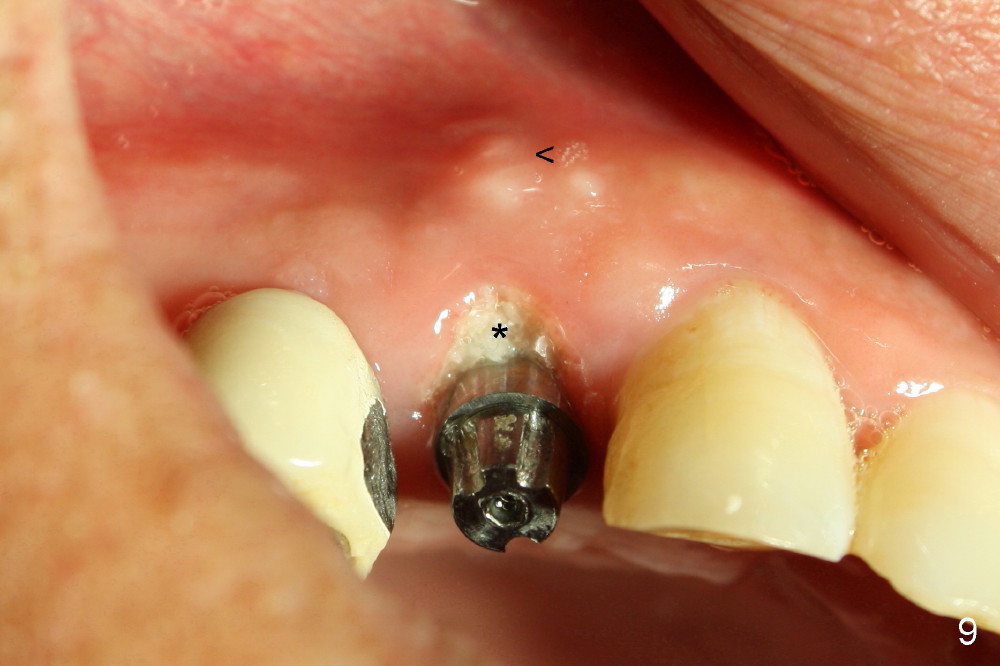

As expected, the collagen dressing is dislodged when the perio dressing is off; fortunately the bone graft remains in place 7 days postop (Fig.9 *). To keep the bone graft in place, an immediate provisional (Fig.10 P) is fabricated and cemented; its margin (*) covers the graft. There is no occlusal contact in centric and lateral excursion. The patient is asked not to use this crown for 3 months.